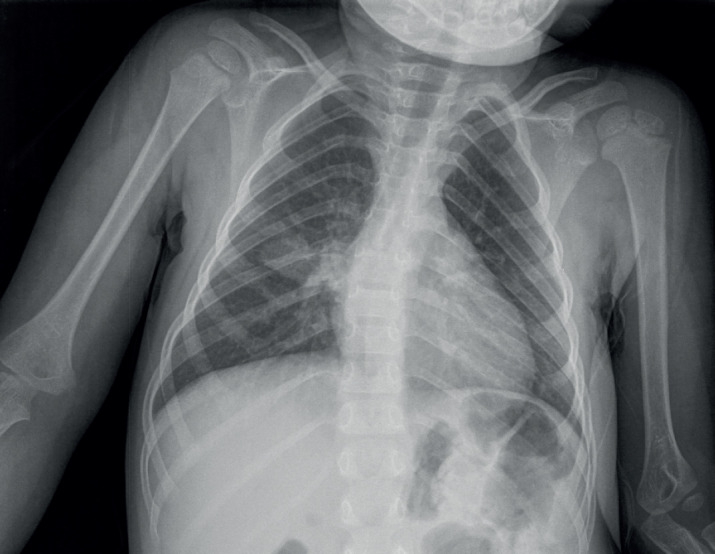

Case presentation: In children, TB often presents with a wide range of non-specific clinical and radiological manifestations, making diagnosis challenging, particularly in regions with low prevalence. We report the case of a two-year-old female with a history of constipation, weight loss, marked abdominal distension with hepatosplenomegaly, who was later diagnosed with miliary tuberculosis.

Conclusion: This case highlights an unusual presentation of miliary TB in a very young child, a demographic in which it is infrequently observed. Miliary TB remains a severe and potentially fatal condition, particularly when diagnosis and treatment are delayed. The diagnosis is usually made based on the clinical presentation, supported by a classic miliary pattern on chest X-ray.